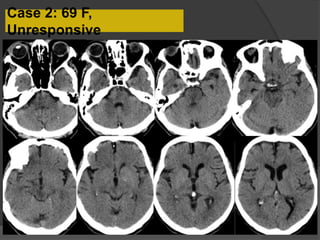

Case 2: 69 F,

Unresponsive

Bilateral paramedian thalamic, midbrain and pontine hypodensities

DDx for bilateral thalamic lesions:

•Metabolic and toxic disorders (Wernicke’s encephalopathy, Osmotic myelinolysis)

•Viral encephalitis

•Vascular occlusion-Top of the basilar syndrome, Artery of Percheron infarcts, Deep

venous thrombosis

•Cerebral hypotension, PRES

Acute infarcts in the pons, midbrain and bilateral thalami

“V sign”

Lazzaro N et al. AJNR Am J Neuroradiol 2010;31:1283-1289

•An uncommon anatomic variant: a single dominant

thalamoperforating artery supplies bilateral

paramedian thalami and the rostral midbrain

•Clinical diagnosis difficult

Case 2 Dx: Artery of Percheron Infarct

Most common etiology is cardioembolic

Additional small infarcts in the right MCA distribution